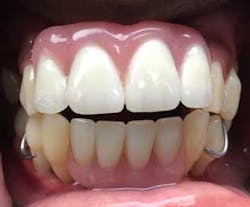

Of course, proper records were obtained in order to fabricate the temporary provisional prosthesis (figure 7), upper and lower, to provide proper function, esthetics, and easy conversion.

Provisional prostheses were then positioned and upon proper stability, function, and cosmetic appearance were torqued to 15 Ncm. At this point, the occlusion was evaluated; posterior occlusion was adjusted to be extremely light, and occlusion associated in the anterior region carried more inter-arch load (figure 11). (2)